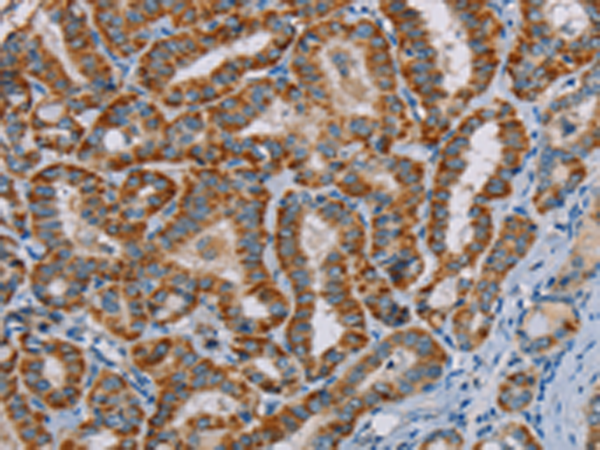

分类: 科研抗体货号: P08510别名: NRMT; NTM1A; AD-003; HOMT1A; C9orf32; METTL11A应用: IHC反应种属: Human, Mouse, Rat